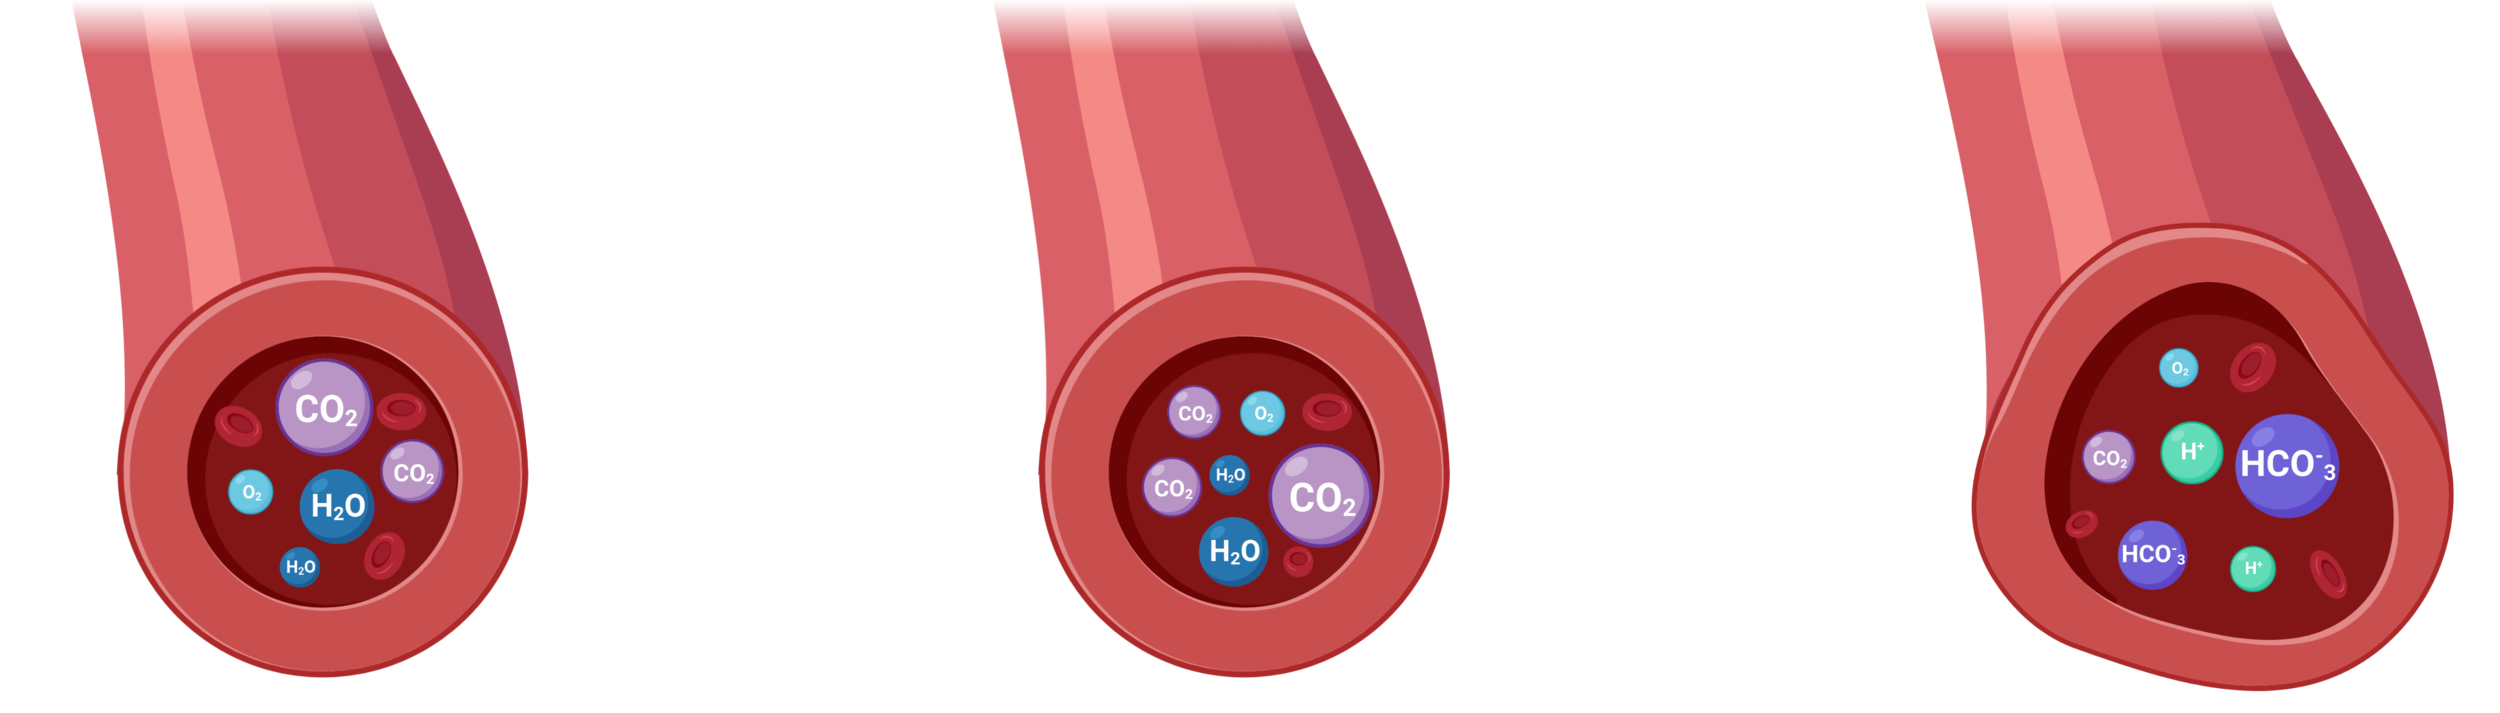

Cerebrovascular Reactivity (CVR) is the response of cerebral vessels to a vasoactive stimulus (e.g. CO2) to provide sufficient O2 to cerebral tissues¹

CVR can be measured during BOLD fMRI experiments with Breath-holds (BH), that induce the subject into a state of hypercapnia²

The vessels dilate → Increase of blood flow → Increase of %BOLD signal

CVR mapping [%BOLD/mmHg] can be obtained through a linear regression analysis using the recordings of exhaled CO2 (reliable proxy of CO2 partial pressure in arterial blood)

CVR is a vascular response

to CO2 changes that can be estimated with respiratory tasks and BOLD imaging.